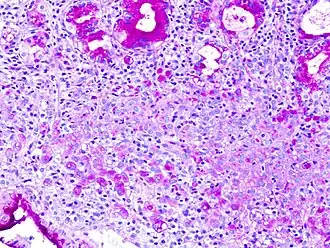

Gastric signet ring cell carcinoma. H&E stain. -

The name of the cell comes from its appearance; signet ring cells resemble signet rings. They contain a large amount of mucin, which pushes the nucleus to the cell periphery. The pool of mucin in a signet ring cell mimics the appearance of a finger hole and the nucleus mimics the appearance of the face of the ring in profile.